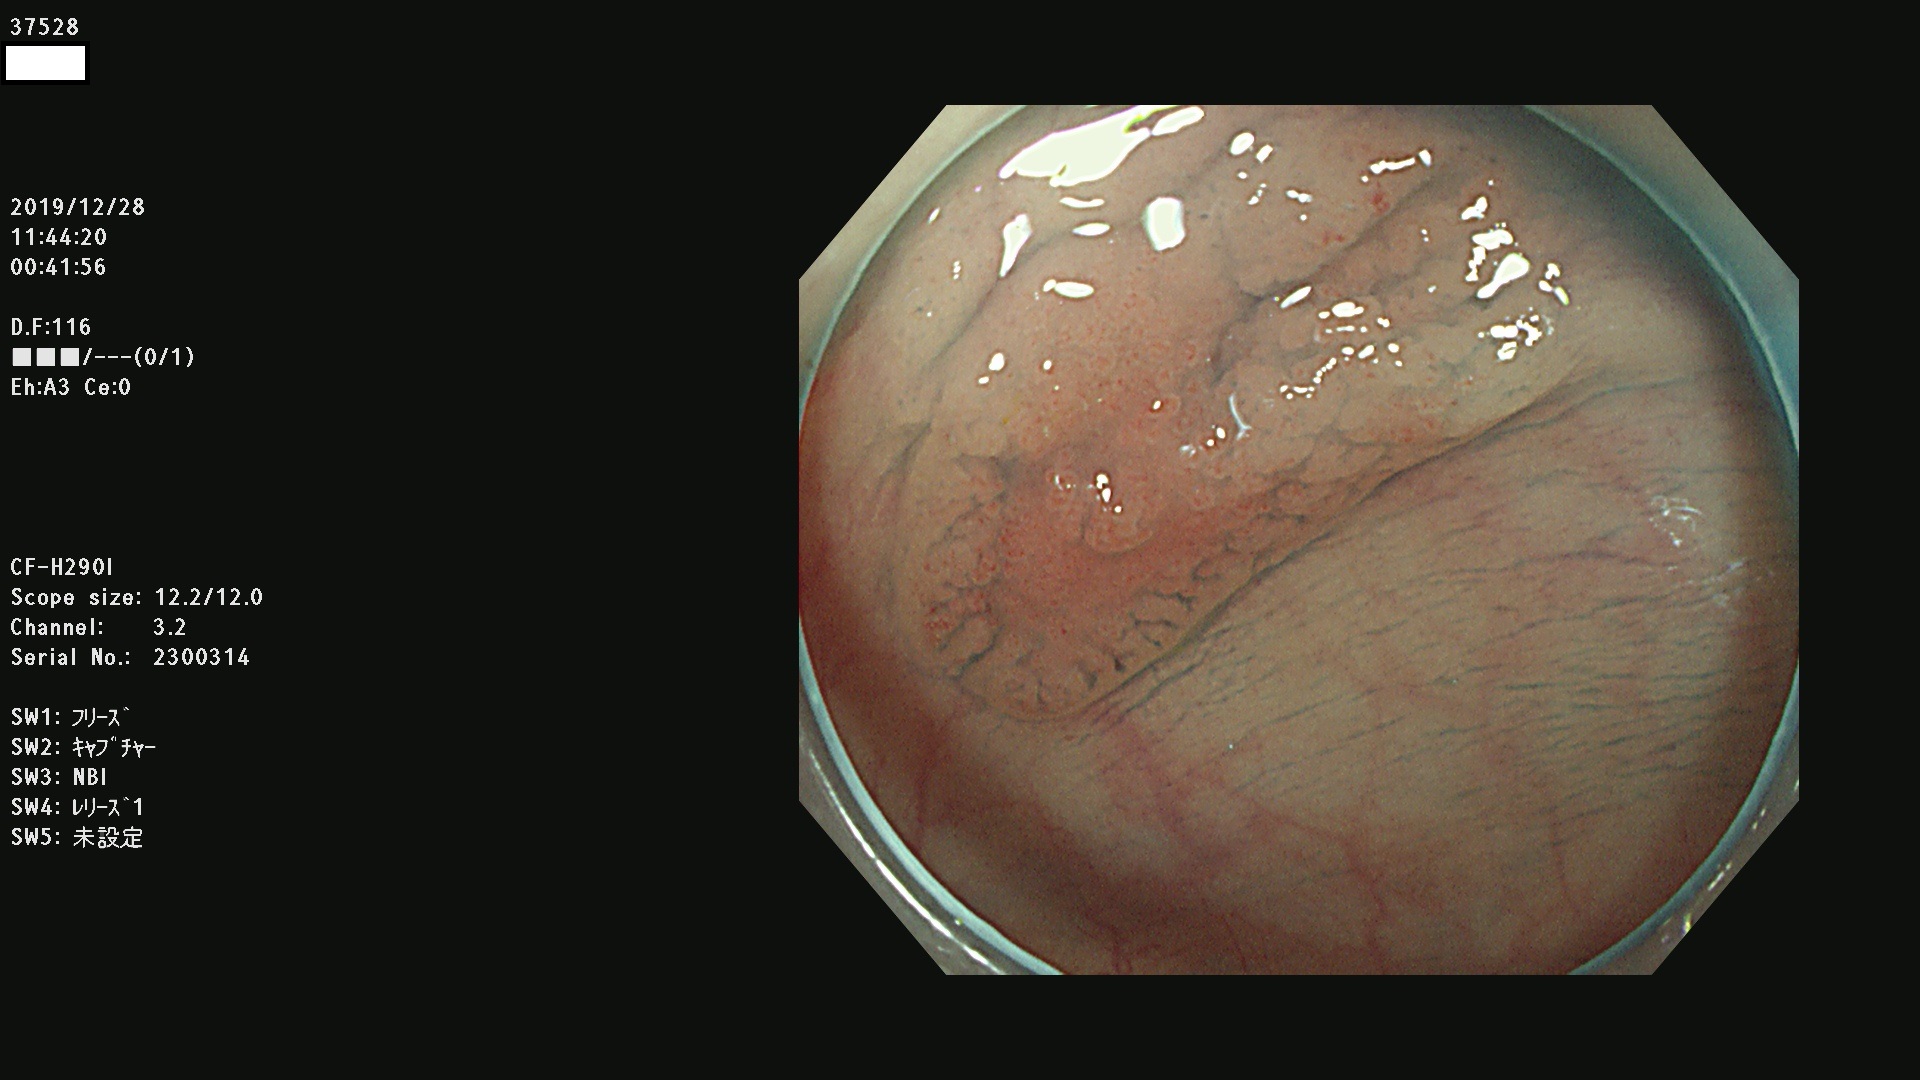

発見困難で危険性の高い平坦型病変(上記100名より抽出) ![]()